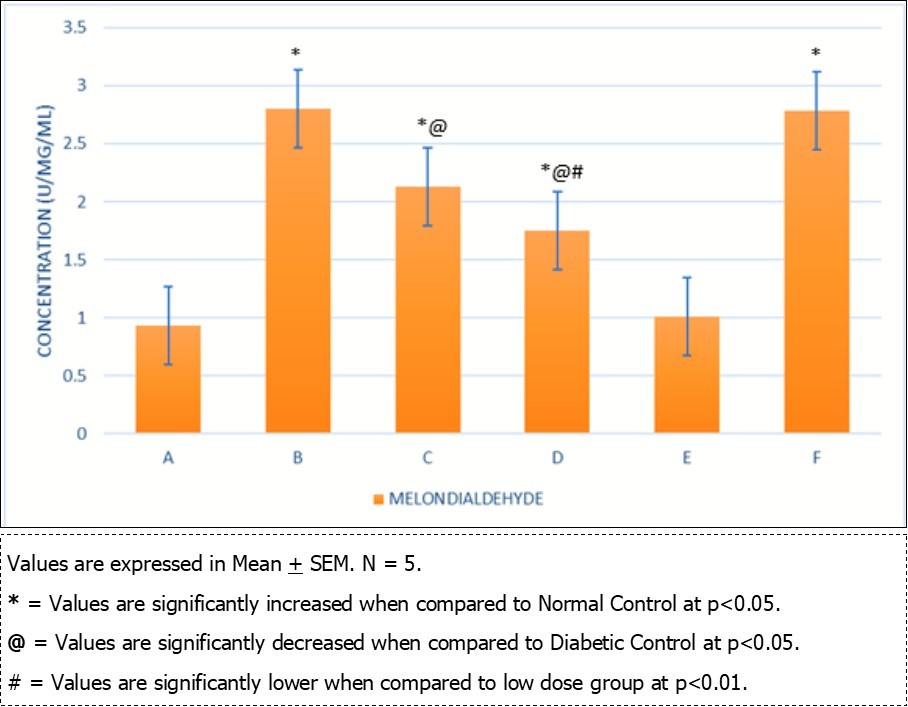

Local Nigerian men have been using AuriculariaPolytricha as a treatment for sexual dysfunction without supporting evidence from scientific experiments. This study was to investigate the effect of ethanolic extract of A. Polytricha on testicular DNA expression and some oxidative stress markers using STZ-Induced diabetic rats as a model. The experiment included six groups, Group A (Normal Control, treated with normal saline), Group B (treated with 65mg/kg.bw of STZ), Groups C, D, and E (treated with 250mg/kg.bw, 500mg/kg.bw, 1000mg/kg.bw AP after inducing diabetics), and Group F (treated with 40mg/kg.bw metformin after inducing diabetics). The experiment lasted for 35 days. After termination of the experiment, Fuelgen nuclear reaction was used for DNA demonstration to assess testicular DNA distribution while serum Superoxide Dimutase (SOD), Catalase and Melondialdehyde where evaluated using reagent based antioxidant enzyme assay. Results reveals that SOD and Melondialdehyde activities were remarkably (p<0.05) higher in diabetic control animals when compared with the normal control group. Values in Groups C, D and F that were administered with 250, 500mg/kg.bw A. polytricha and metformin respectively were also significantly (p<0.05) increased when compared with the normal control group. However, diabetic animals placed on 1000mg/kg.bw A. polytrichadid not show any statistical significance in comparison with normal control group but was remarkably (p<0.01) decreased when compared to the diabetic group that received low dose A. polytricha, an indication that the reversal is dose dependent. Catalase concentration in diabetic control animals was remarkably (p<0.05) higher when compared to the normal control but was not significantly (p<0.05) different in groups D (DM+500mg/kg.bw A. polytricha) and E (DM+1000mg/kg.bw A. polytricha) when compared with the normal control group. Diabetic control animals showed reduced magenta colour intensity of DNA and increased clustering and cross linking of DNA strands when compared with the normal control. However the degree of cross link in DNA strands was reduced in the diabetic animals placed on 1000mg/kg.bw A. polytrichawhen compared with the diabetic control group. Reversal in DNA damage and values of serum oxidative stress markers following administration of graded doses of A. polytricha could be attributed to essential phytochemical and therapeutic constituents in A. polytricha like polyphenol and flavonoid which can be found useful in prevention and treatment of diabetes induced testicular dysfunction. In summary, AP can contribute to a reversal in DNA damage and levels of serum oxidative stress markers in treating diabetes-induced testicular dysfunction.

Oxidative stress markers (SOD, catalase and Melondialdehyde) activities of different experimental animals. Figure 1, Figure 2. Results from Fuelgen DNA demonstration is shown in Figure 3, Figure 4, Figure 5, Figure 6, Figure 7, Figure 8.

Figure 2.Comparison of Melondialdehyde in the different experimental groups.

Results obtained from analysis of serum oxidative stress markers shows that both SOD and Melondialdehyde activities were remarkably (p<0.05) higher in diabetic control animals when compared with the normal control group. Values in Groups C, D and F that were administered with 250, 500mg/kg.bw A. polytricha and metformin respectively were also significantly (p<0.05) increased when compared with the normal control group. However, diabetic animals placed on 1000mg/kg.bw A. polytrichadid not show any statistical significance in comparison with normal control group but was remarkably (p<0.01) decreased when compared to the diabetic group that received low dose A. polytricha, an indication that the reversal is dose dependent.

Catalase concentration in diabetic control animals was remarkably (p<0.05) higher when compared to the normal control but was not significantly (p<0.05) different in groups D (DM+500mg/kg.bw A. polytricha) and E (DM+1000mg/kg.bw A. polytricha)when compared with the normal control group. In a similar study, Mallidis et al., (2011) noted that melondialdehyde and caspase-3 activities were significantly higher, whereas SOD and GPx enzymatic activities were remarkably lower in diabetic rats when compared with normal control group. Three weeks administration of A. polytricha revealed a reduction in the values of melondialdehyde concentration in diabetic animal models. The decrease in these values was done in a dose-dependent manner. This findings are consistent with the work done by Mohasseb et al., 2011; Agbaje et al., 2007. They documented that antioxidant supplementation play a role on testicular germ cell apotosis of STZ-induced diabetic rat and can restore both testicular and systemic enzymatic activities of melondialdehyde and caspase-3. A. polytricha antioxidant property is achieved because of the presence of naturally occurring antioxidants like tocopherol, acobic acid, and total phenols 16. Sun et al., (2010) also reported that uronic acid has been fractionized from fruiting body of A. polytricha and that the higher the uronic acid content, the more effective the antioxidant activity of the polysaccharide. A. polytricha also has high phenolic and flavonoid content; glutathione reductase and superoxide dimutse activity 18. Chen et al. (2015) demonstrated that A. polytricha polysaccharides improved significantly, total antioxidant capacity and lipoprotein lipase activity in mice but was found to reduce melondialdehyde levels and arteriosclerosis index in rats and he attributed the strong antioxidant status to the phenolic compound in A. polytricha.